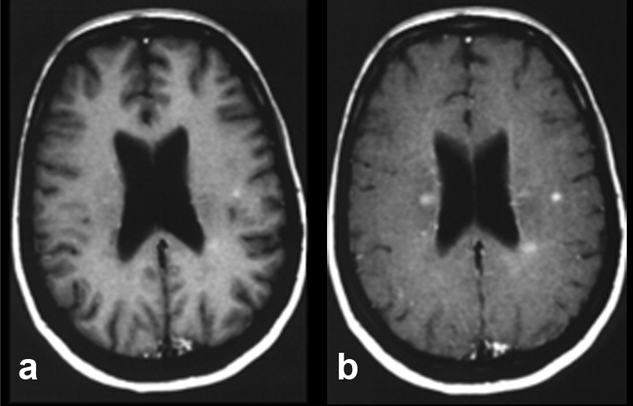

Figure 11-07:

Example of magnetization trans­fer contrast. Patient with multiple scle­ro­sis.

(a) T1-weighted brain images after enhancement with a gadolinium-based con­trast agent.

(b) Image with additional magnetization transfer con­trast. The com­bi­na­tion of contrast agent and MTC clearly enhances contrast and shows more le­sions, al­though it remains unclear whether all of these lesions are active.